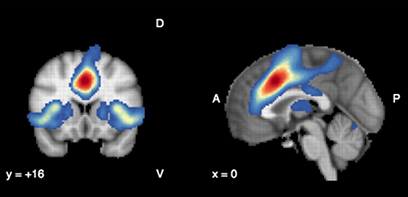

Feature: Antioxidants in the brain linked to improved treatment results for psychosis

June 03, 2020

Patients who experience their first episode of psychosis will have better overall outcomes if they respond early to treatment. A research team led by Dr. Lena Palaniyappan studied antioxidant levels in the brain, and found that these chemicals may improve outcomes of early intervention in psychosis.